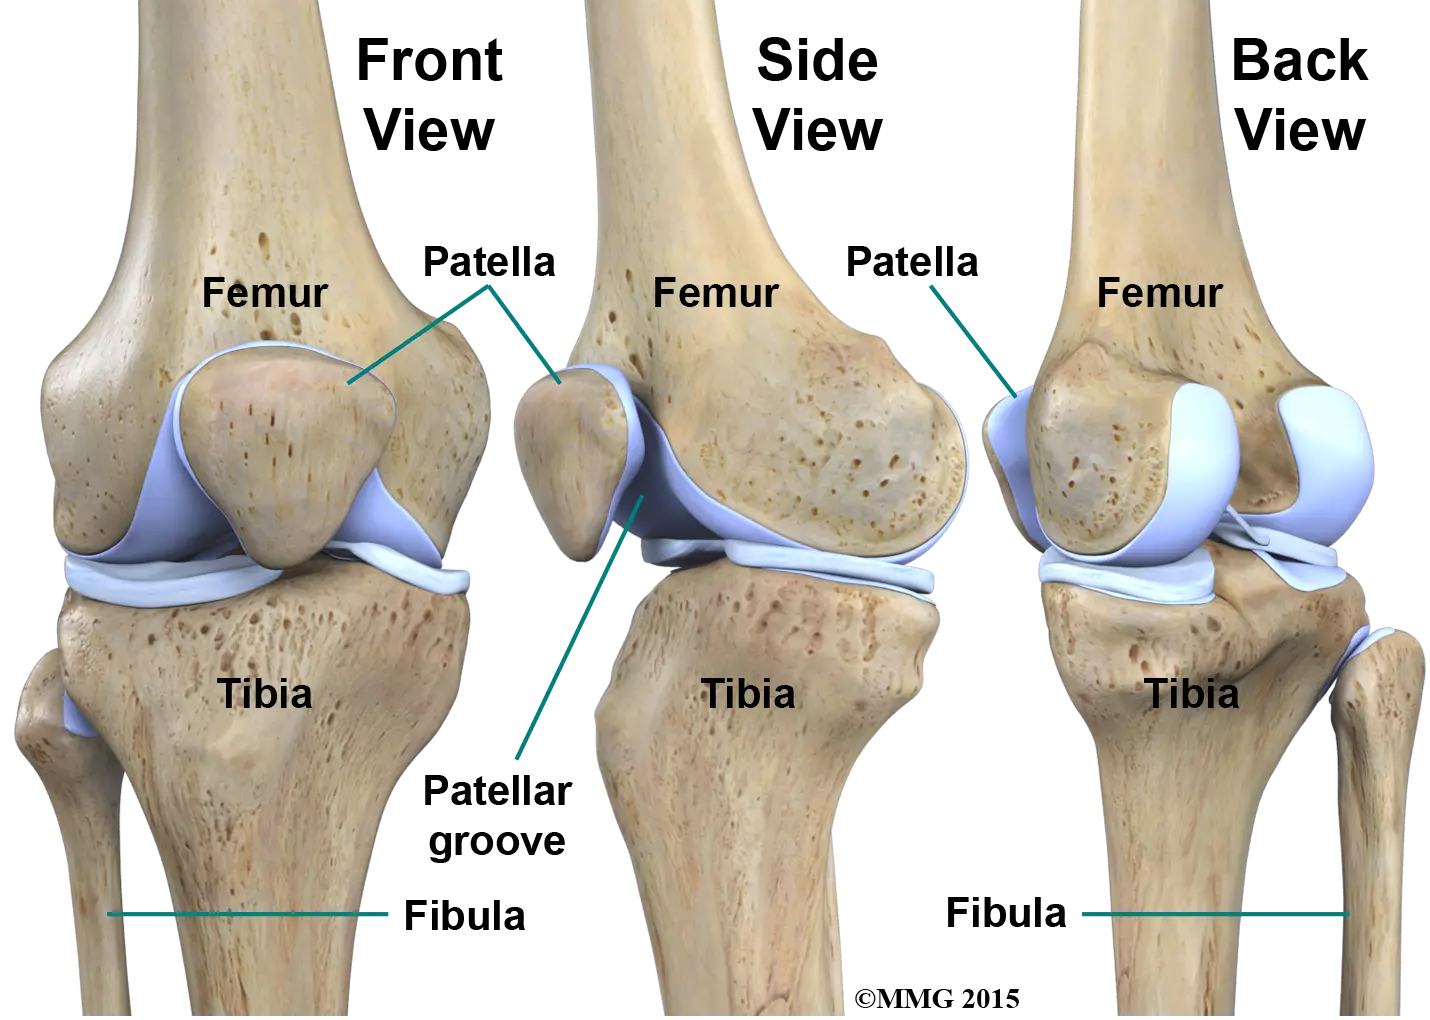

Anatomy

The knee is the largest joint in the body and having healthy knees is required to perform most everyday activities.

The knee is made up of the lower end of the thighbone (femur), the upper end of the shinbone (tibia), and the kneecap (patella). The ends of these three bones are covered with articular cartilage, a smooth substance that protects the bones and enables them to move easily within the joint.

The menisci are located between the femur and tibia. These C-shaped wedges act as shock absorbers that cushion the joint.

Large ligaments hold the femur and tibia together and provide stability. The long thigh muscles give the knee strength.

All remaining surfaces of the knee are covered by a thin lining called the synovial membrane. This membrane releases a fluid that lubricates the cartilage, reducing friction to nearly zero in a healthy knee.

Normally, all of these components work in harmony. But disease or injury can disrupt this harmony, resulting in pain, muscle weakness, and reduced function.